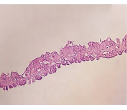

ورقه اپیتلیالی کراتینوسایتی یک جایگزین پوستی از سلولهای کراتینوسایت مشتق از بافت اپیدرمی فوراسکین است. این ورقه دارای ویزگیهایی از جمله ایمن بودن اجزای سازنده این ترکیبات برای کاربرد های انسانی، موثر بودن در درمان و مناسب بودن از لحاظ کاربردی و جابجایی است. این جایگزین هم چنین به نوعی مانع اتلاف حرارت ومایعات و هم چنین کاهش میزان عفونت والتهاب و درد در موضع سوختگی و زخم نیز می گردد.